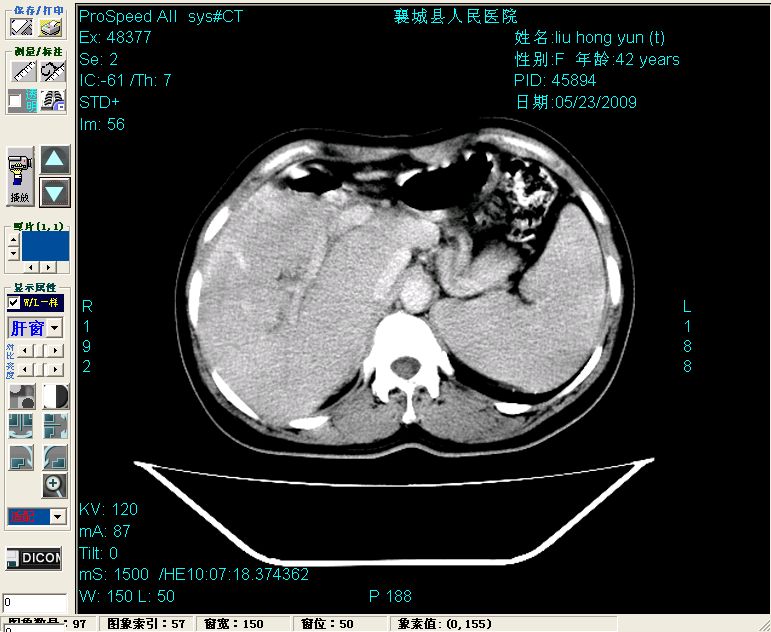

增强:

增强动脉期前述低密度区轻度早其强化,门脉期强化程度显著增高,延期扫描强化程度下降,但仍为相对高密度影

结合病史考虑,1现在引起黄疸体征的原因应该是胆总管胰段结石阻塞,建议局部胃肠造影剂排空后复查.

2左肝及右肝前叶表现考虑胆囊摘除术后所致的肝动门脉瘘形成,慢性纤维组织炎性增生.不完全除外左肝胆管细胞癌

3脾大,可能与动门脉瘘所致门脉高压有关